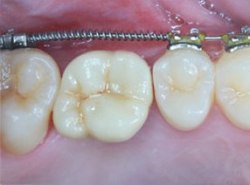

矯正治療過程

治療中